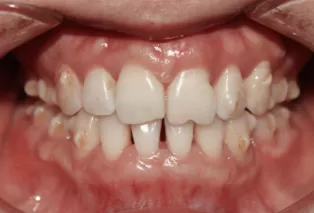

Photos intra-orales